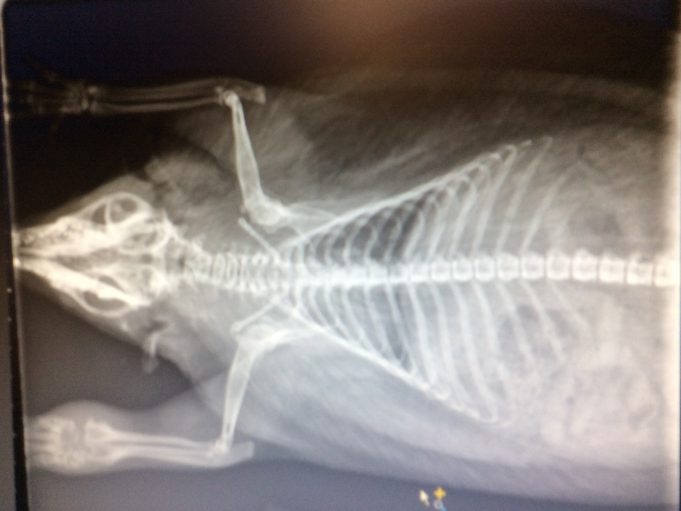

Diagnostic

Gros hérisson bien portant. Il a sans doute une infection avec poche de pus dans sa patte antérieure gauche.

• Le 06/11/2018 : Véto: Checkup de la patte. On voit les os qui sont désagrégés.

• Le 10/11/2018 : Dumbo n'a pas un abcès à la patte mais une tumeur. (ostéosarcome qui lui attaque l'intérieur de la patte). Il n'y a rien à faire.